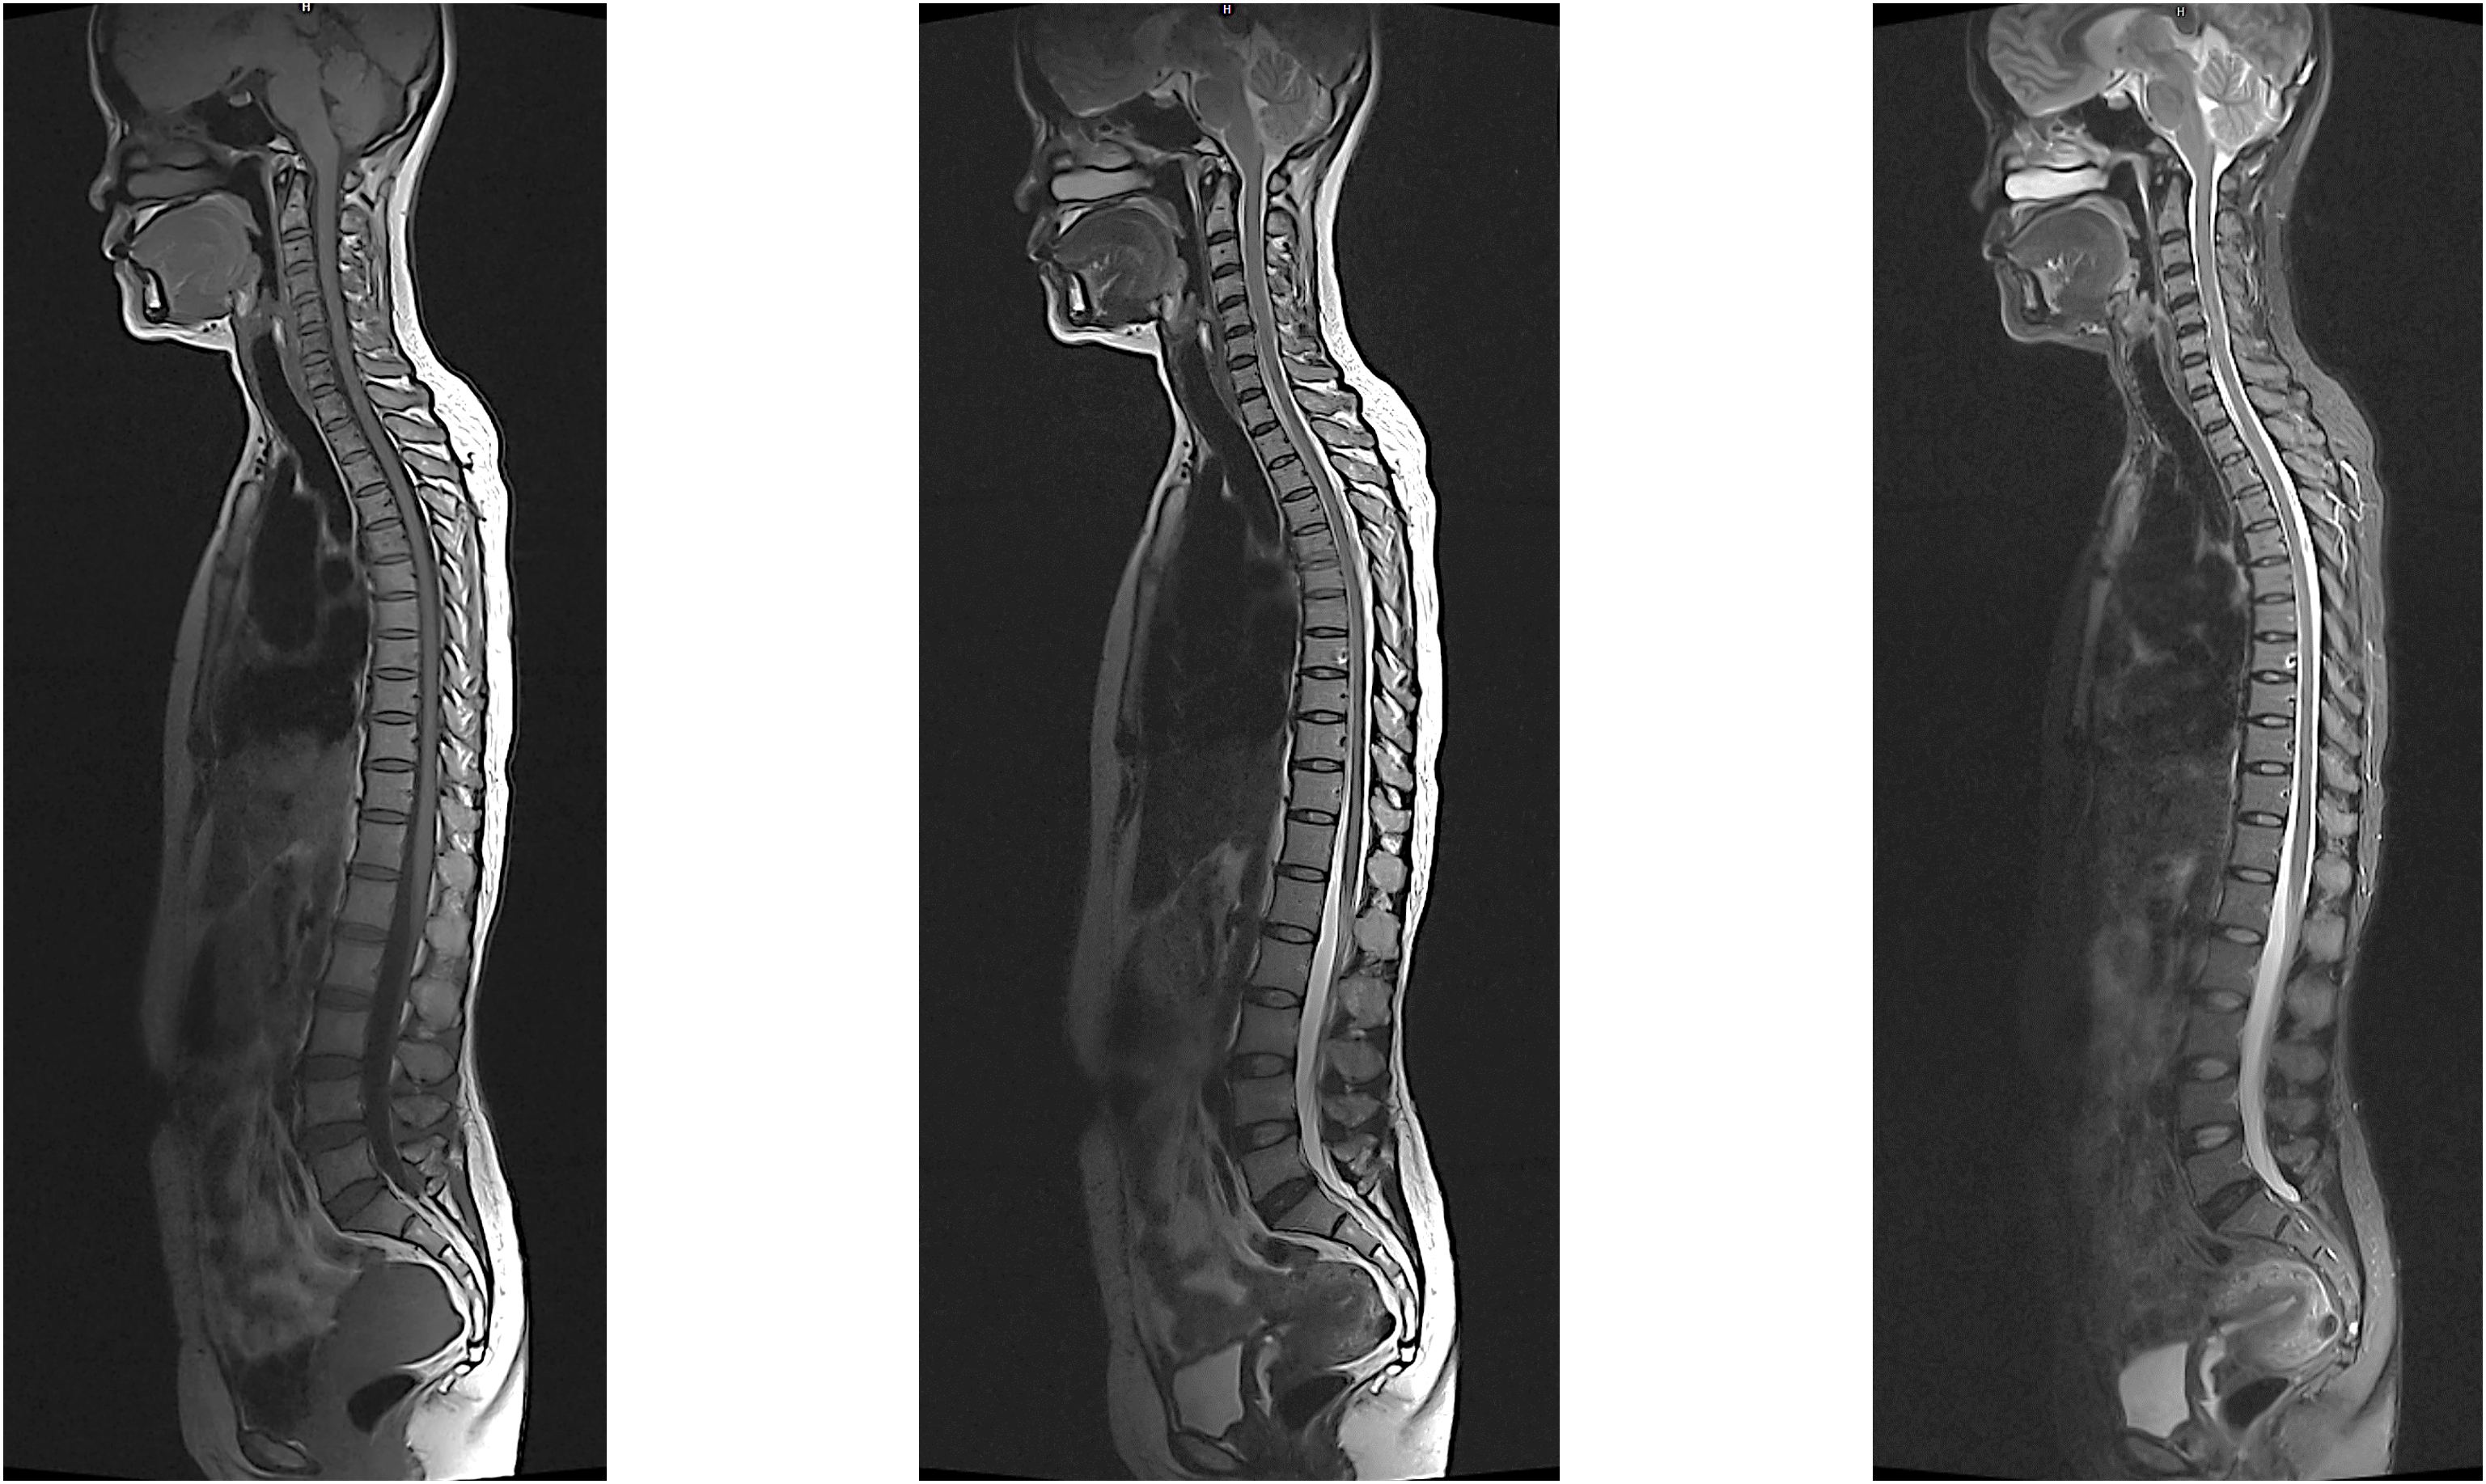

Hình ảnh lâm sàng